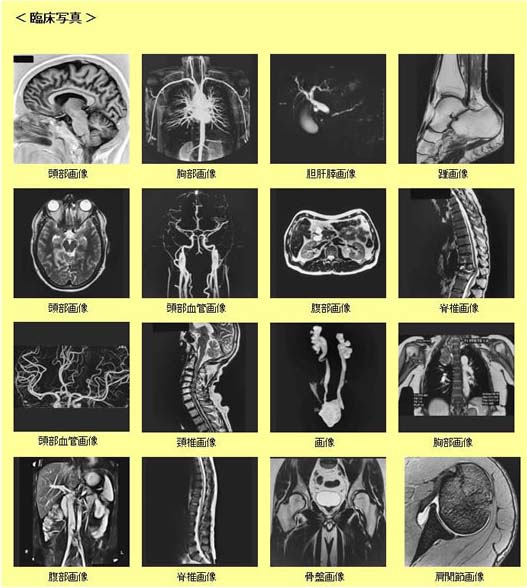

磁気共鳴画像撮影装置(Magnetic Resonance Imaging)

MRIとは・・・

核磁気共鳴を用いた画像診断装置で身体の断層像を撮影する装置ですが任意の断面(縦、横、斜め切り等)の撮影が可能で画像診断に役立てます。X線を使用せず強力な磁石(磁場)を使用し撮影するので、被曝の心配はありません。また造影剤を使用せずに、血管を撮影(MRA:磁気共鳴血管撮影)することができます。当院のMRI装置はPHILIPS社製の高磁場1.5T(テスラ)が2台稼動しています。

超電導磁気共鳴画像診断装置 Multiva 1.5T

超電導磁気共鳴画像診断装置 Multiva 1.5T

超電導磁気共鳴画像診断装置 Prodiva 1.5T

超電導磁気共鳴画像診断装置 Prodiva 1.5T